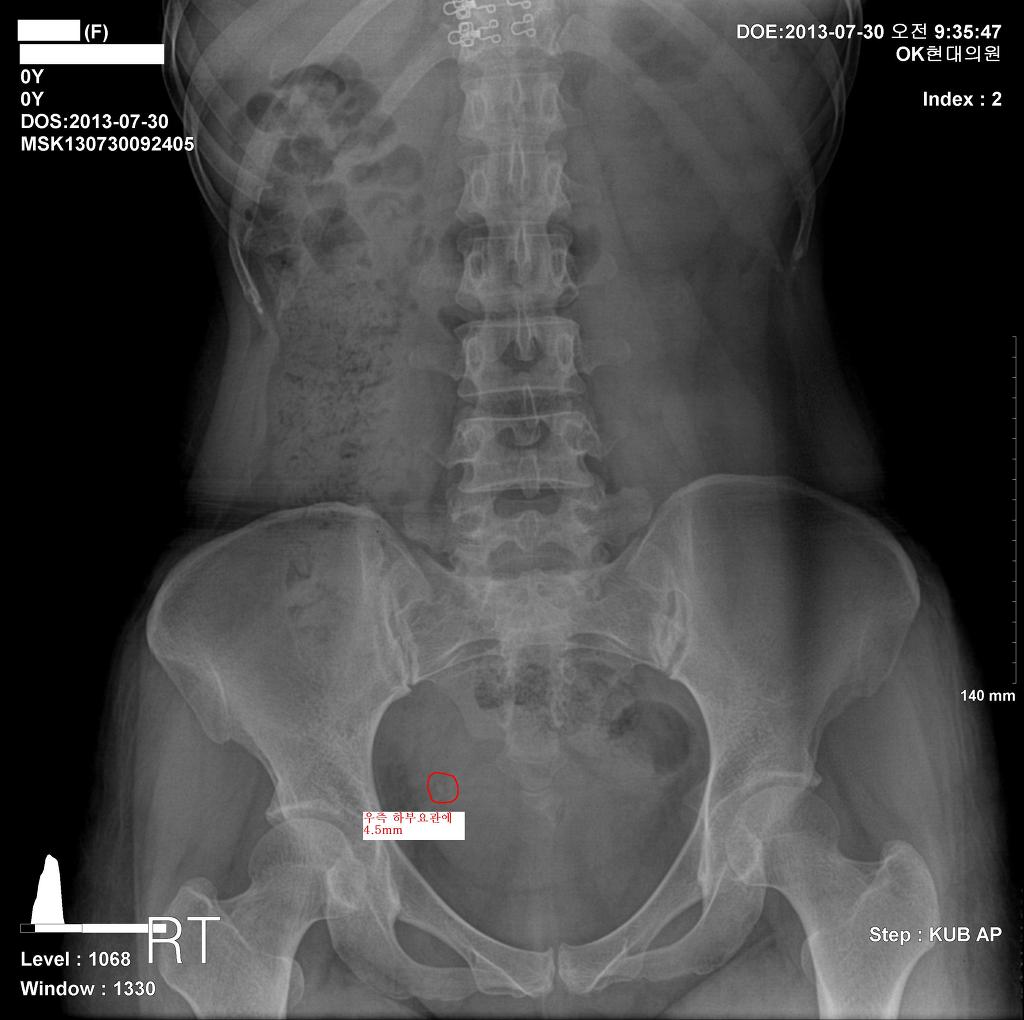

새벽부터 갑자기 우측 옆구리 통증을 호소한 42세 여자환자

우측 하부요관에 4.2mm 결석으로

1,800번 쇄석 치료후 통증은 사라 졌습니다.